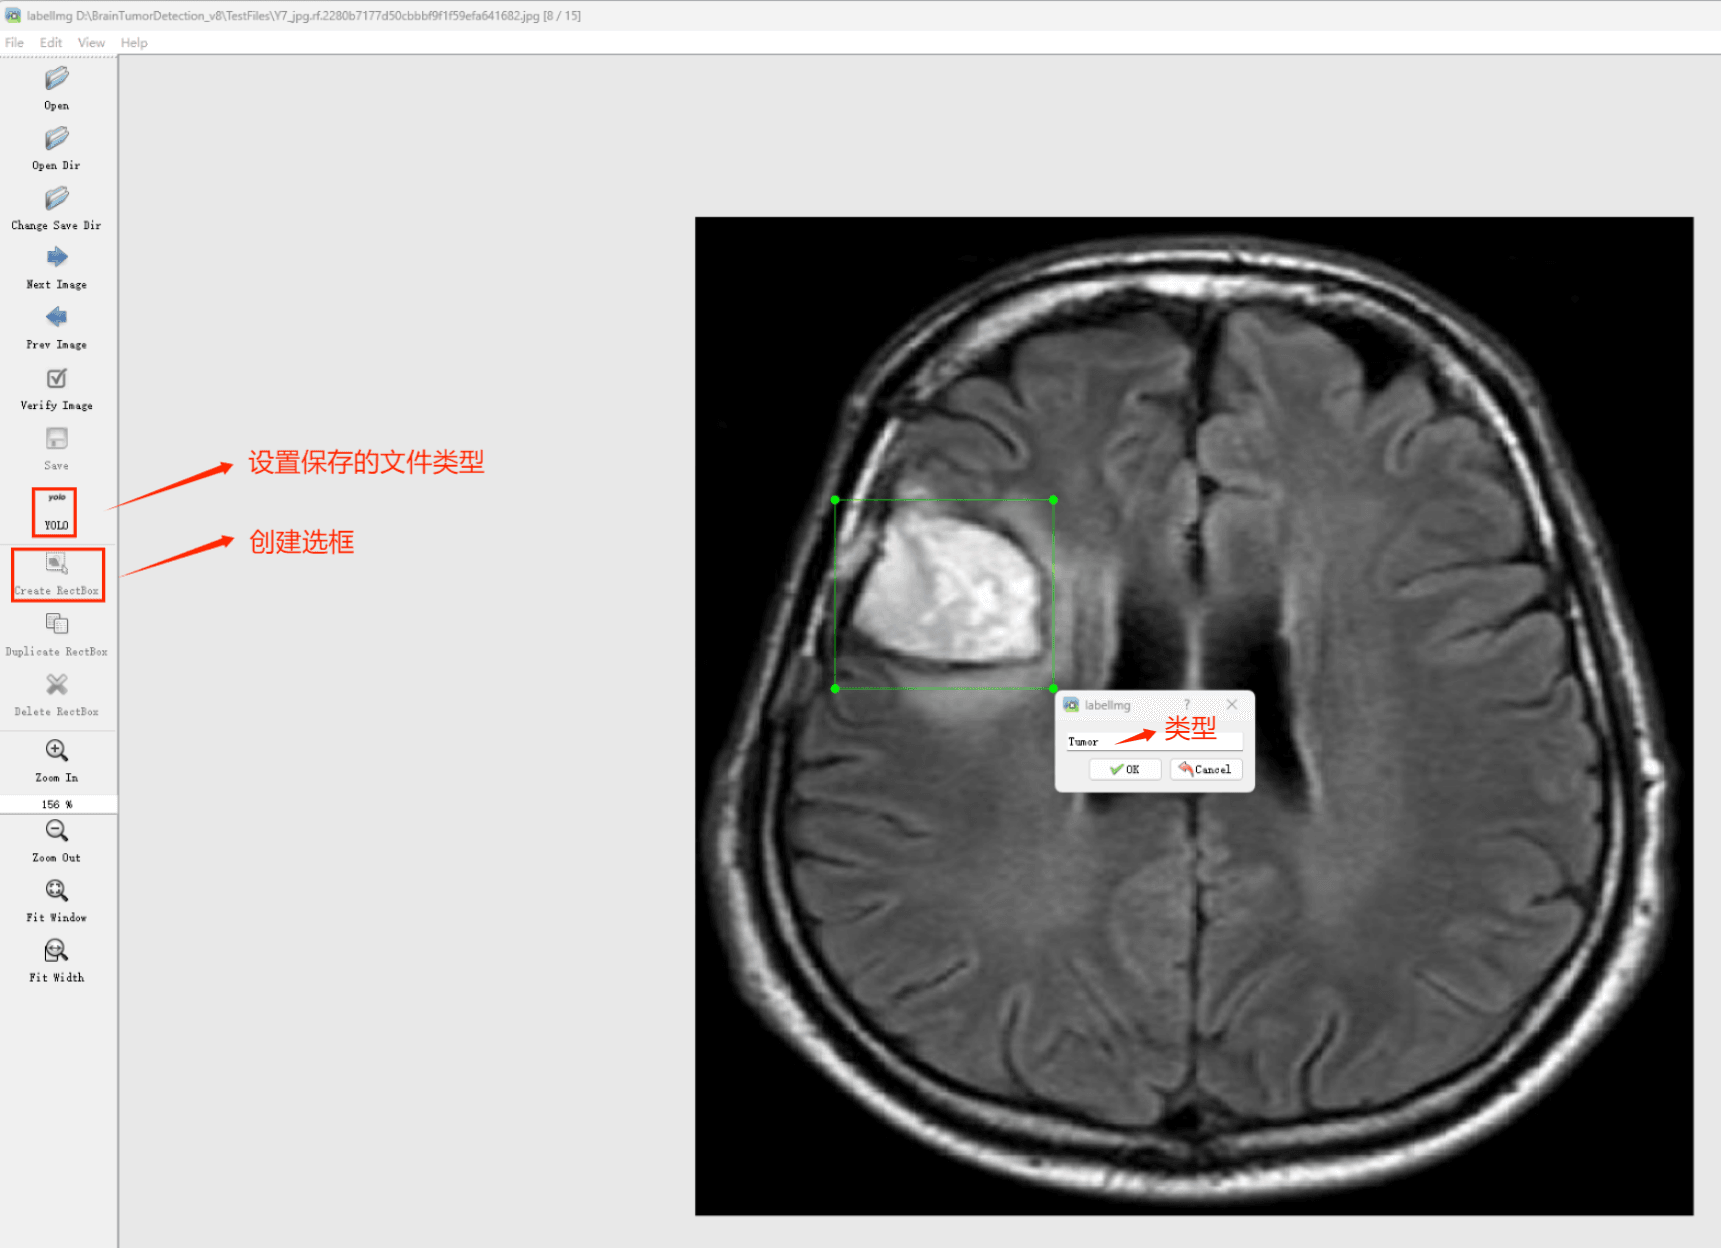

Tipps:通过搜集关于数据集为各种各样的脑肿瘤相关图像,并使用Labelimg标注工具对每张图片进行标注,分2检测类别,是’无肿瘤’, ‘肿瘤’。

目标检测标注工具

(1)labelimg:开源的图像标注工具,标签可用于分类和目标检测,它是用python写的,并使用Qt作为其图形界面,简单好用(虽然是英文版的)。其注释以 PASCAL VOC格式保存为XML文件,这是ImageNet使用的格式。此外,它还支持 COCO数据集格式。

初识labelimg

打开后,我们自己设置一下

在View中勾选Auto Save mode

接下来我们打开需要标注的图片文件夹

并设置标注文件保存的目录(上图中的Change Save Dir)

接下来就开始标注,画框,标记目标的label,然后d切换到下一张继续标注,不断重复重复。